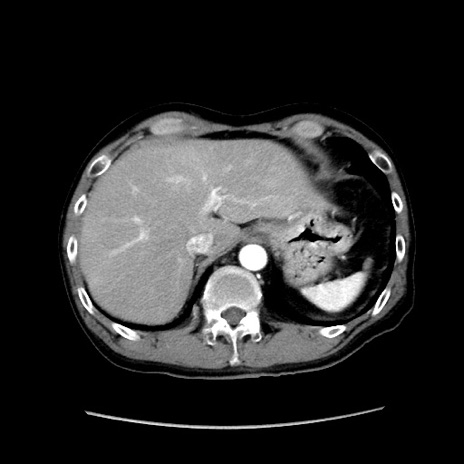

冠状断像

症例37(横断像)

【症例】40歳代 男性

【主訴】腹痛

【現病歴】4時間ほど前に電車に乗車中に臍部上より腹痛出現。徐々に増悪し起立困難となり、救急外来受診。生ものは数日食べていない。今朝お雑煮を食べた。

【身体所見】BT 36.8℃、BP 117/84mmHg、HR 91/min、SpO2 97%、苦悶様、腹部:臍上部広範囲圧痛あり、反跳痛±

【データ】WBC 8100、CRP 0.03